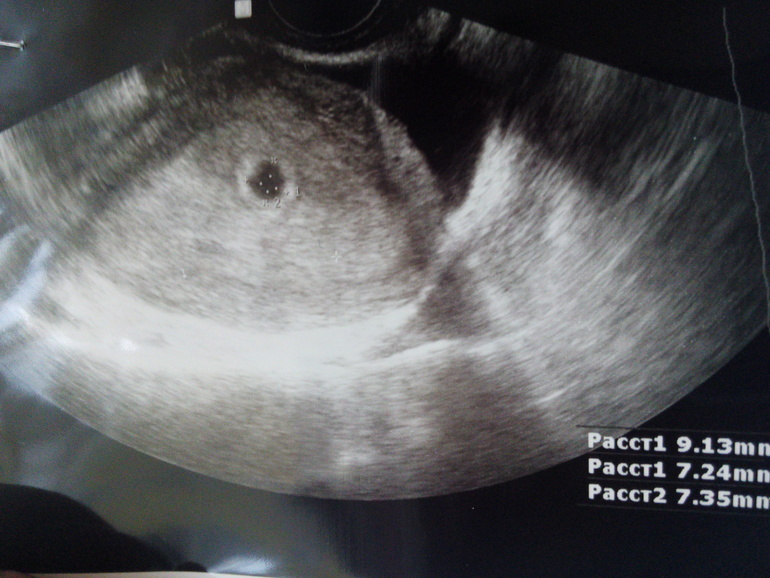

А какой у вас срок? Я сегодня была на УЗИ. Эмбриона не увидели. Примерный срок 5,4 недели